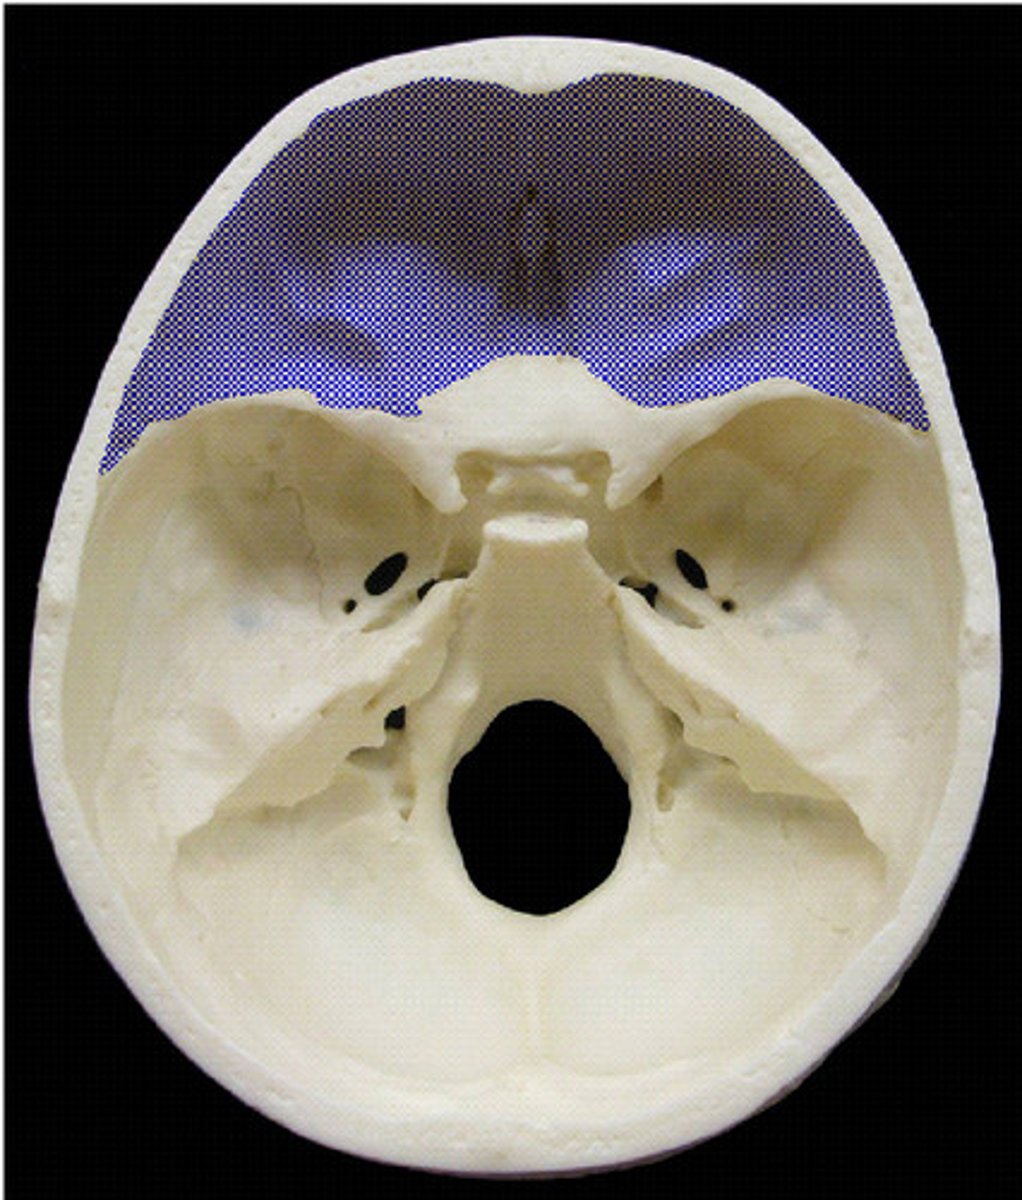

anterior cranial fossa